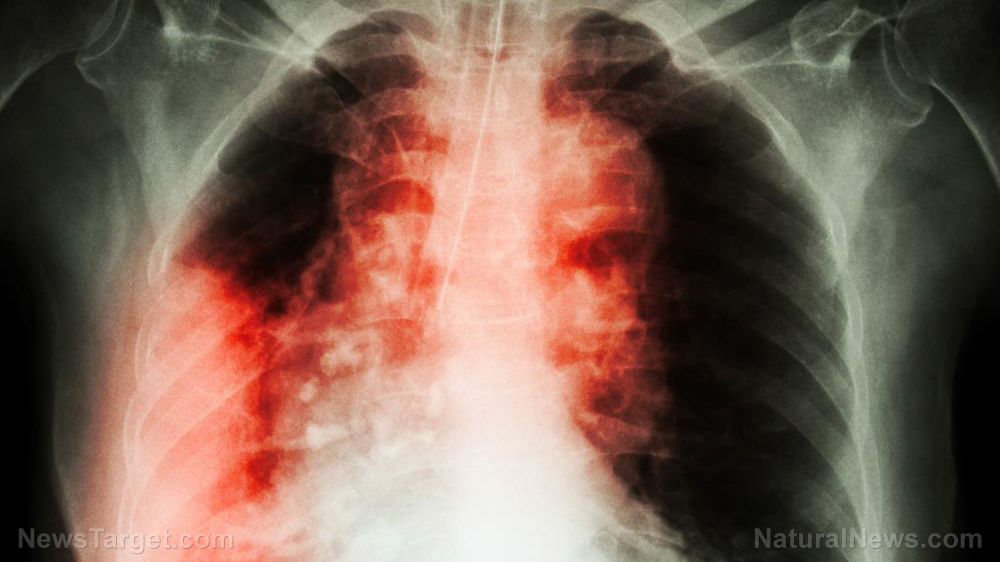

A Canadian research team announced that it has found the reason for the appearance of pulmonary fibrosis in a number of lung cancer patients who underwent thoracic radiotherapy. They found a connection between genes on a certain chromosome and the development of lung injuries triggered by radiation.

Pulmonary fibrosis is a progressive disease caused by the scarring of injured lung tissue. The scar tissue that developed on the organ is thicker and stiffer than healthy tissue.

Fibrosis hampers the normal expansion and contraction of the lung. This reduces the amount of oxygen that could be drawn with each breath, which in turn decreases the amount of oxygen available for use by the body.

There are lung cancer patients who experience pulmonary fibrosis after getting exposed to radiation, such as during thoracic radiotherapy treatment. Other patients suffering from different types of cancer develop this lung condition after taking Bleomycin (Blenoxane), a pharmaceutical drug used for chemotherapy.

"One of the limiting side effects of thoracic radiotherapy is the development of pulmonary fibrosis in a susceptible subpopulation of treated patients," Haston remarked. "However, the specific pathways contributing to fibrosis susceptibility in radiotherapy patients remain unidentified."